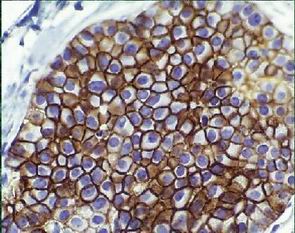

E-cadherin (E-c) transmembranous glycoprotein participates in molecule of calcium dependent intercellular adhesion

E-c function in mantaining/ in consonance with epithelial integrity/cell adhesion

Abnormal E-c function attributable to a mutation of the E-c gene (predominantly in the part that encodes the extracellular domain) facilitates abnormal loss of E-c expression signalizes detachment process leading to metastasis

E-c tumor/invasion suppressor gene is to be mutated in human lobular carcinoma with corresponding l o s s of E-c expression

E-c tumor/invasion suppressor gene is not to be mutated in human ductal carcinoma with corresponding p r e s e r v a t i o n of E-c expression

E-c gene is to be mutated in LCIS

E-c gene is not to be mutated in DCIS

L o s s of E-c expression reflects an abnormal E-c function demonstrates germline mutation in the gene encoding E-c in a patient with lobular carcinoma corresponding with l o s s of E-c expression